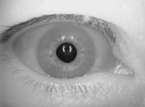

「めまい」は目が回るとよく表現しますが、このような患者さんの目を見ると本当に目がクルクル回っています。このために赤外線CCDカメラを利用した特殊な検査用眼鏡を着けて検査を行い目の動き(眼振と呼びます)を観察します(赤外線フレンツェル検査)。良性発作性頭位めまい症に典型的な眼振が観察されれば診断できます。

目が回るようなめまいの際には、実際に眼球が無意識に動いています(眼振)。この検査では、赤外線カメラを使って目の動きをモニターに映し出し、眼振の種類や特徴を詳しく観察。診断の重要な手がかりになります。